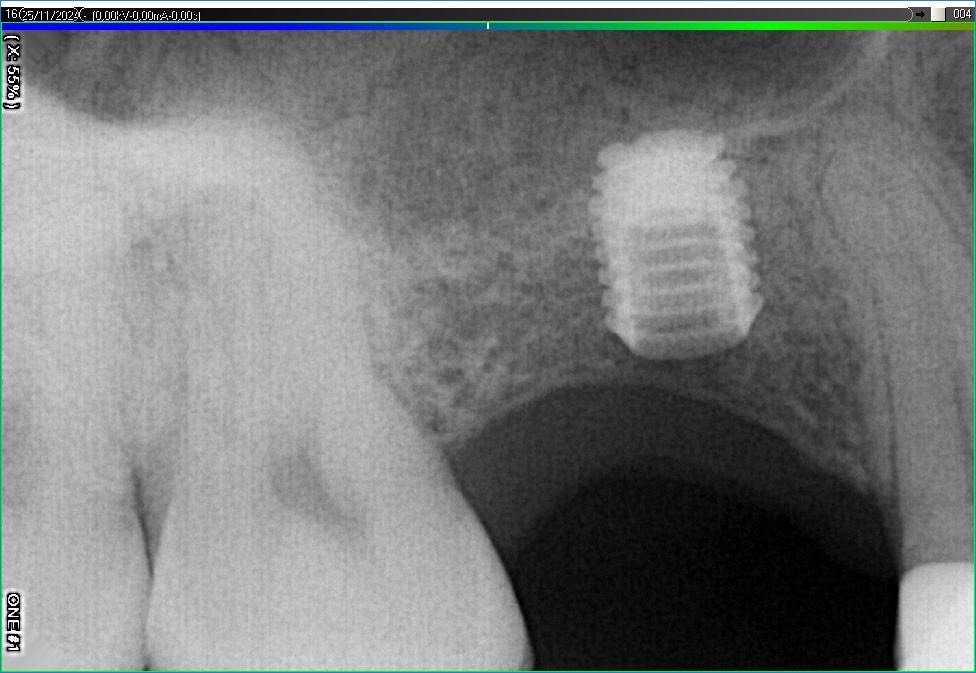

Імплантація